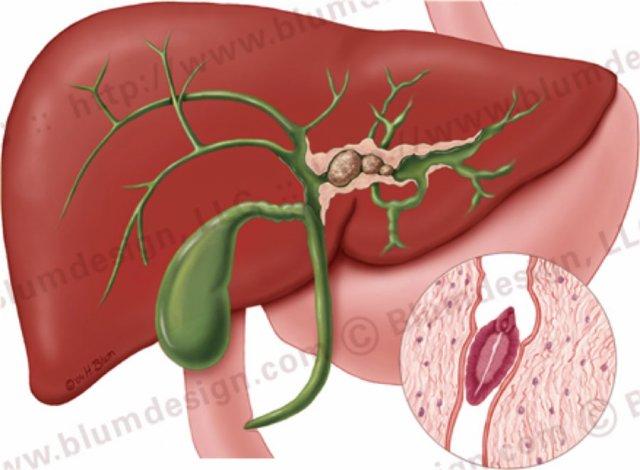

Viêm xơ đường mật nguyên phát với các chỗ hẹp ở cả đường mật trong gan và ngoài gan. Minh họa bởi Heike Blum

Đặc điểm điển hình của PSC là các chỗ hẹp, tuy nhiên ở giai đoạn sớm của bệnh, các chỗ hẹp này có thể khó nhận biết.

Bất thường nền tảng trong PSC là xơ hóa, với căn nguyên chưa được xác định.

PSC có mối liên quan chặt chẽ với viêm loét đại tràng ở tới 70% bệnh nhân, nhưng cũng có thể liên quan đến bệnh Crohn của đại tràng.

Lý do của mối liên quan với bệnh viêm ruột (IBD) vẫn chưa được biết rõ, nhưng được cho là kết quả của một phản ứng miễn dịch.